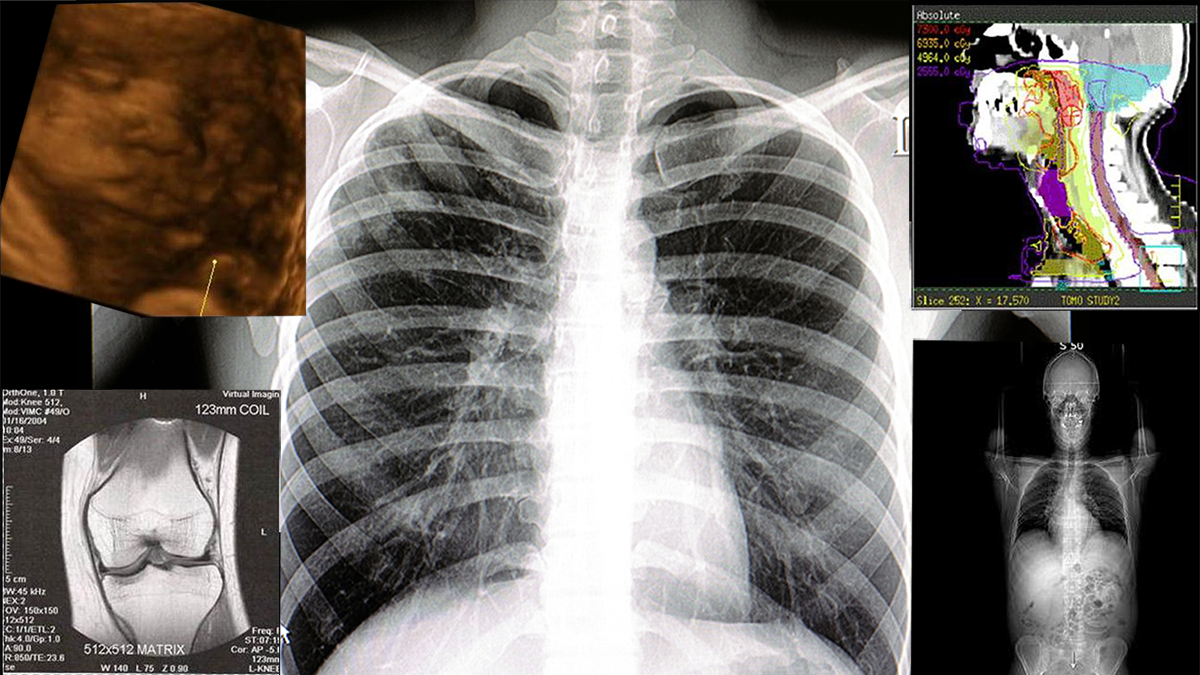

The Department of Medical Imaging & Radiation Sciences (MIRS) exists to provide a comprehensive, multi-skilled education preparing students for entry-level practice into the medical imaging and radiation therapy professions. This mission is accomplished through collaborative education, research and scientific efforts with the health care community.

The Department of Medical Imaging and Radiation Sciences at Arkansas State University began in 1981 with the radiologic technology program. Since the establishment of the first program, the university has added six major emphases to the baccalaureate of science in radiologic sciences (BSRS) degree. Each program within the department maintains applicable JRCERT or CAAHEP programmatic accreditation and has established a reputation for quality education and clinical experiences in the imaging and radiation sciences.

The Bachelor of Science in Radiologic Sciences (BSRS) Program consists of Radiography foundation courses, followed by one of the 5 Specialty Tracks listed below.

Cardiovascular-Interventional Technology

Diagnostic Medical Sonography

Magnetic Resonance Imaging / Computed Tomography

Mammography / Breast Sonography

Radiation Therapy